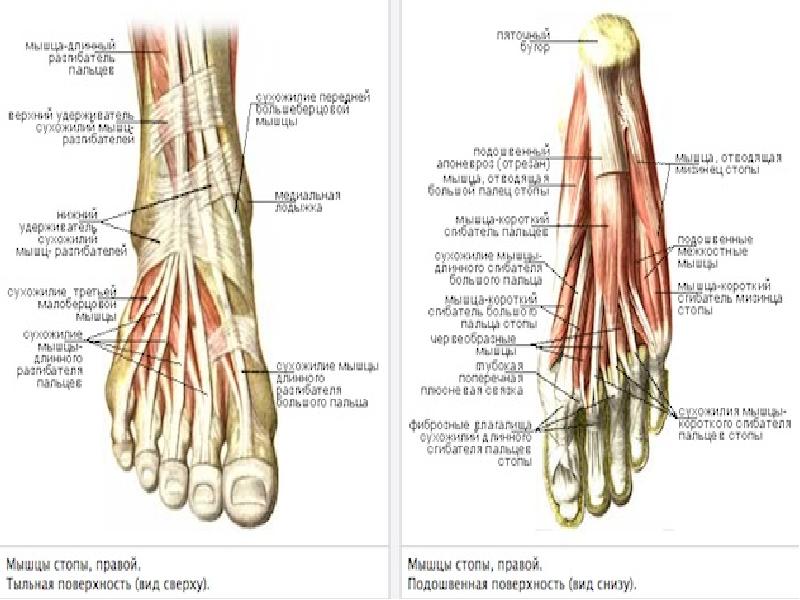

Анатомия суставов Шапарова и Лисфранка: фото и информация